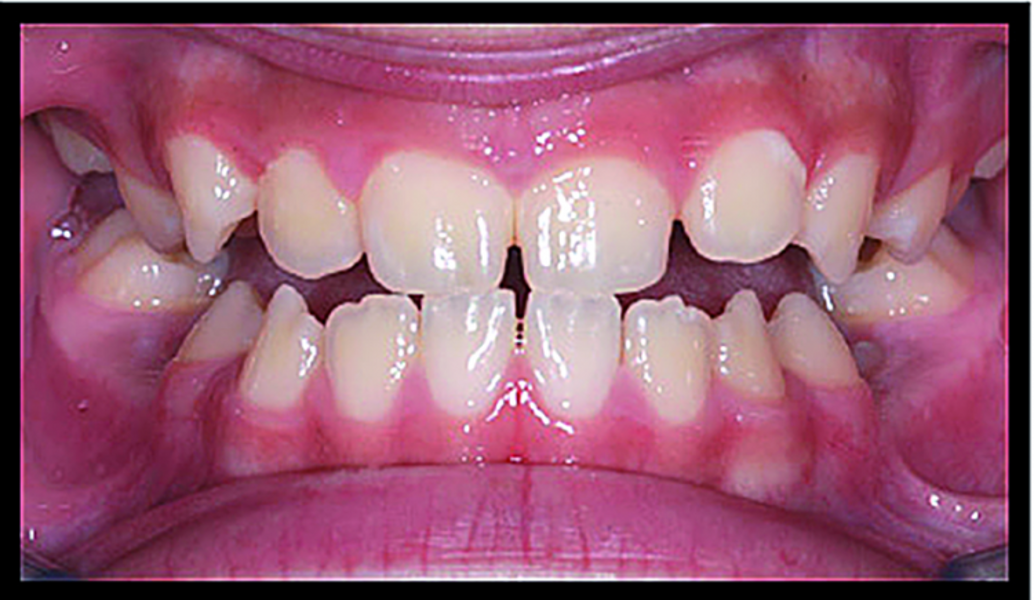

BiTurbo2 system for rapid deep overbite correction